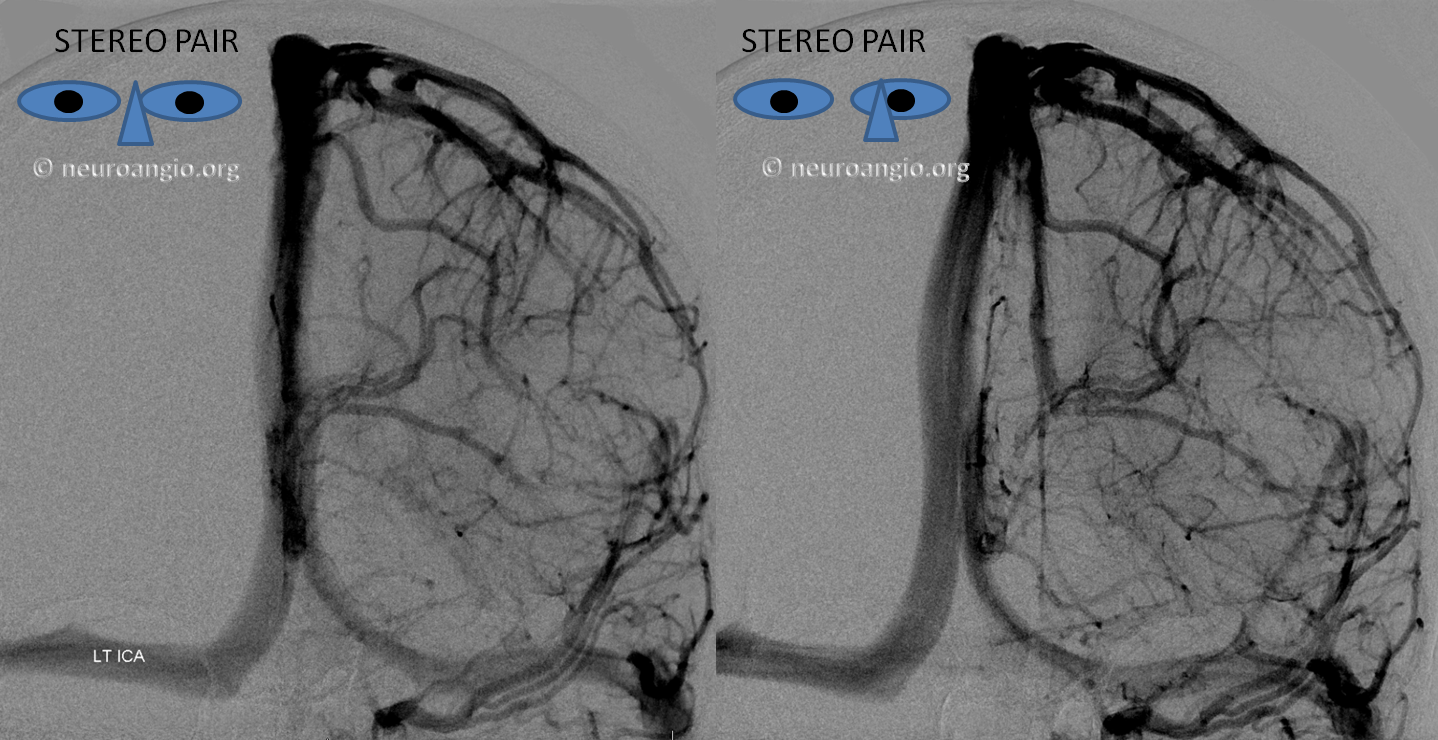

Below is an example of as large an inferior sagittal sinus (white) as one is likely to ever see under non-pathologic circumstances. Why is this sinus so large? Again, the answer is that veins are like rivers — the inferior sagittal sinus happens to be receiving a completely benign, nonpathologic mesial anterior frontal vein (blue arrows). However, the increased inflow into the Galen system has likely resulted in alternate drainage of the basal vein (purple) into the superior petrosal sinus via the lateral mesencephalic vein (black) — see deep venous system and veins of posterior fossa pages for more info. Also notice a large emissary vein (pink)

Stereo of the same